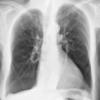

emphysema

Date: 01/19/2015

Views: 5566

Emphysema Lat

Date: 04/15/2009

Views: 5079